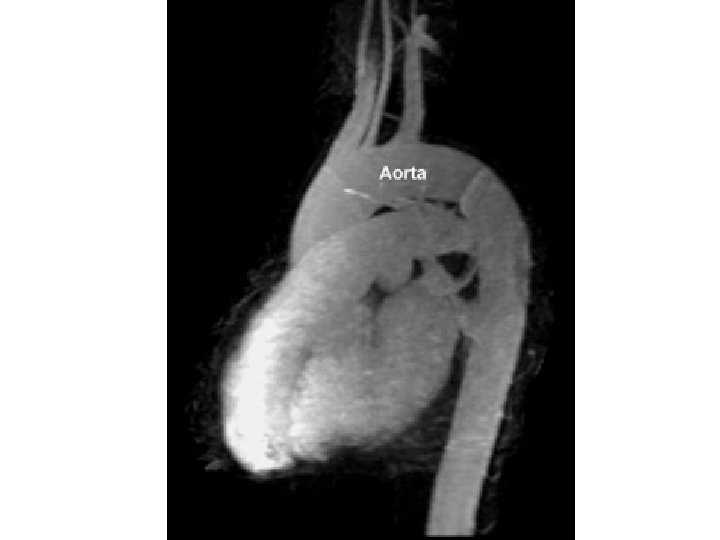

Aorta ascendens; Pars ascendens aortae = Ascending aorta • sinus aortae Valsalvae (dx. , sin. , ant. ) – arteria coronaria dx. + sin. • crista supravalvularis • bulbus aortae • aneurysms

Aneurysma aortae ascendentis surgical solution